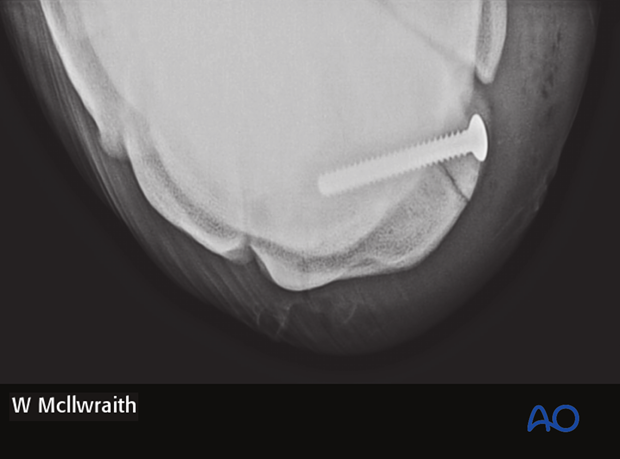

The 3.5 mm screw of appropriate length is inserted and tightened under arthroscopic visualization.

Pearl: Use two fingers and thumb when doing final tightening, thereby avoiding excessive torque and potential breaking of the screw head.

After the screw is tightened any debris or elevated cartilage at fracture line is removed.

Intraoperative radiographs are taken to confirm screw length and correct positioning.